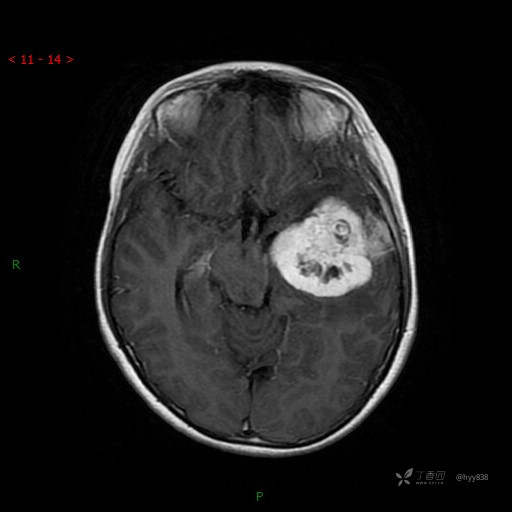

“典藏”病例分享。10岁儿童,头痛头晕一周余,CT、MRI 都有---结果公布~

简要病史:患者于一周前无明显诱因开始出现头痛头晕,无恶心呕吐,无肢体抽搐,无寒颤高热,无腹胀腹泻,无视力下降及视野缺损,上述症状休息后可稍缓解,未引起重视。 2天前患者头痛头晕不适加重,伴有恶心感,无呕吐,遂到当地人民医院行头颅CT检查示:左侧颞部占位性病变,今日家属为求进一步治疗,来我院门诊求治。门诊拟“左侧颞部占位性病变”收入我科。 患病以来,患者精神、饮食、睡眠尚欠佳,大小便如常,体力体重无明显变化。

临床诊断:左侧颞部占位

讨论:病变性质?

MRI增强